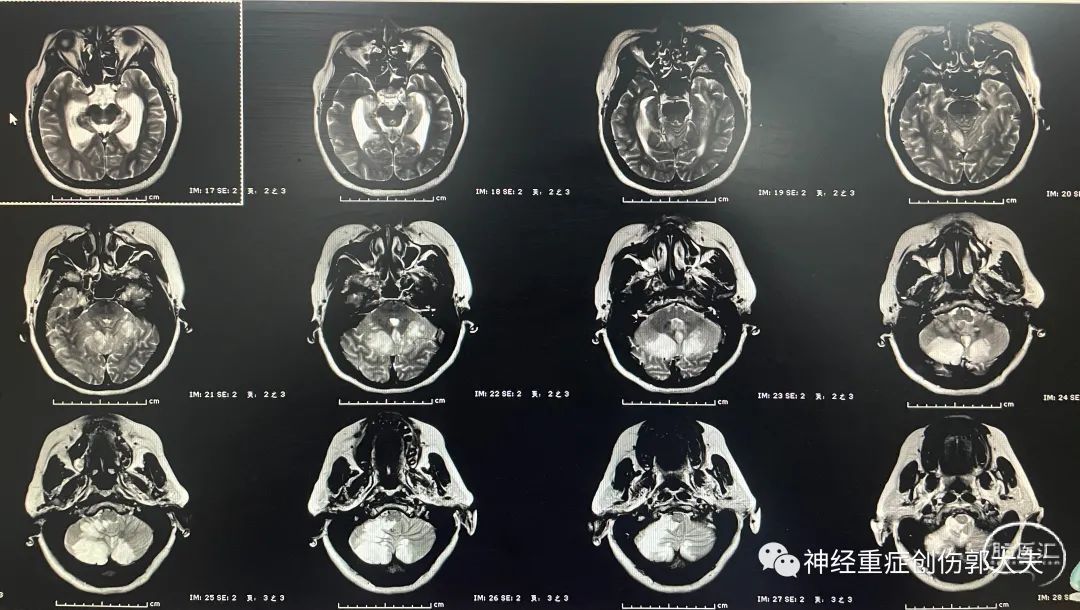

患者女性,34岁,主因“头晕4天,加重2天”入住我院神经内科,神志清楚,完善头颅核磁显示双侧小脑半球及丘脑大面积脑梗死。

通过与患者家属详细交流后先行侧脑室外引流,如病情加重,再行后颅窝减压术。术后复查移动CT显示引流管位于侧脑室内。